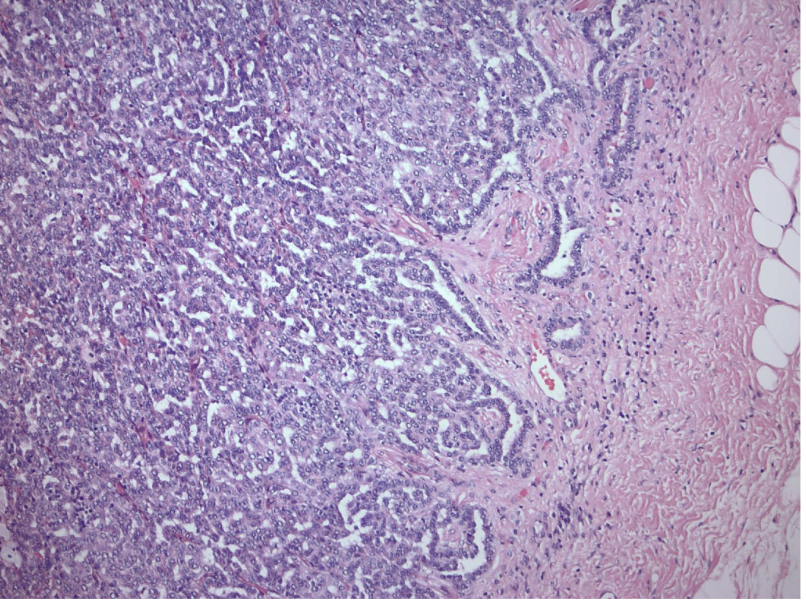

chromophobe RCC

arise from intercalated disc of collecting ducts; multiple chromosome loss and extreme hypodiploidy

chromophobe RCC

RCC with best prognosis

chromophobe RCC

raisinoid nuclei